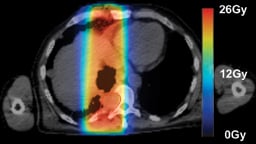

Images (left,1, & below): adoption of SBRT for spinal irradiation to nonspinal bone metastases (2, 4) standard AP/PA (1, 3)

Our current workflow for same-day palliation requires three to four hours and is a highly coordinated conventional workflow with kVCT simulation, treatment planning, treatment plan quality assurance and then treatment delivery. During treatment planning, TomoHelical or TomoDirect delivery mode is chosen, along with 3-D or intensity-modulated radiation therapy (IMRT) planning mode. We employ dosimetric concepts from stereotactic body radiation therapy (SBRT) to deliver a highly conformal target dose distribution, while minimizing dose to adjacent normal tissues. We generally employ an extreme hypofractionated palliative regimen consisting of 8 Gy per fraction with one to three fractions, depending on tumor size, tumor location, dose to normal tissues and patient-specific goals.